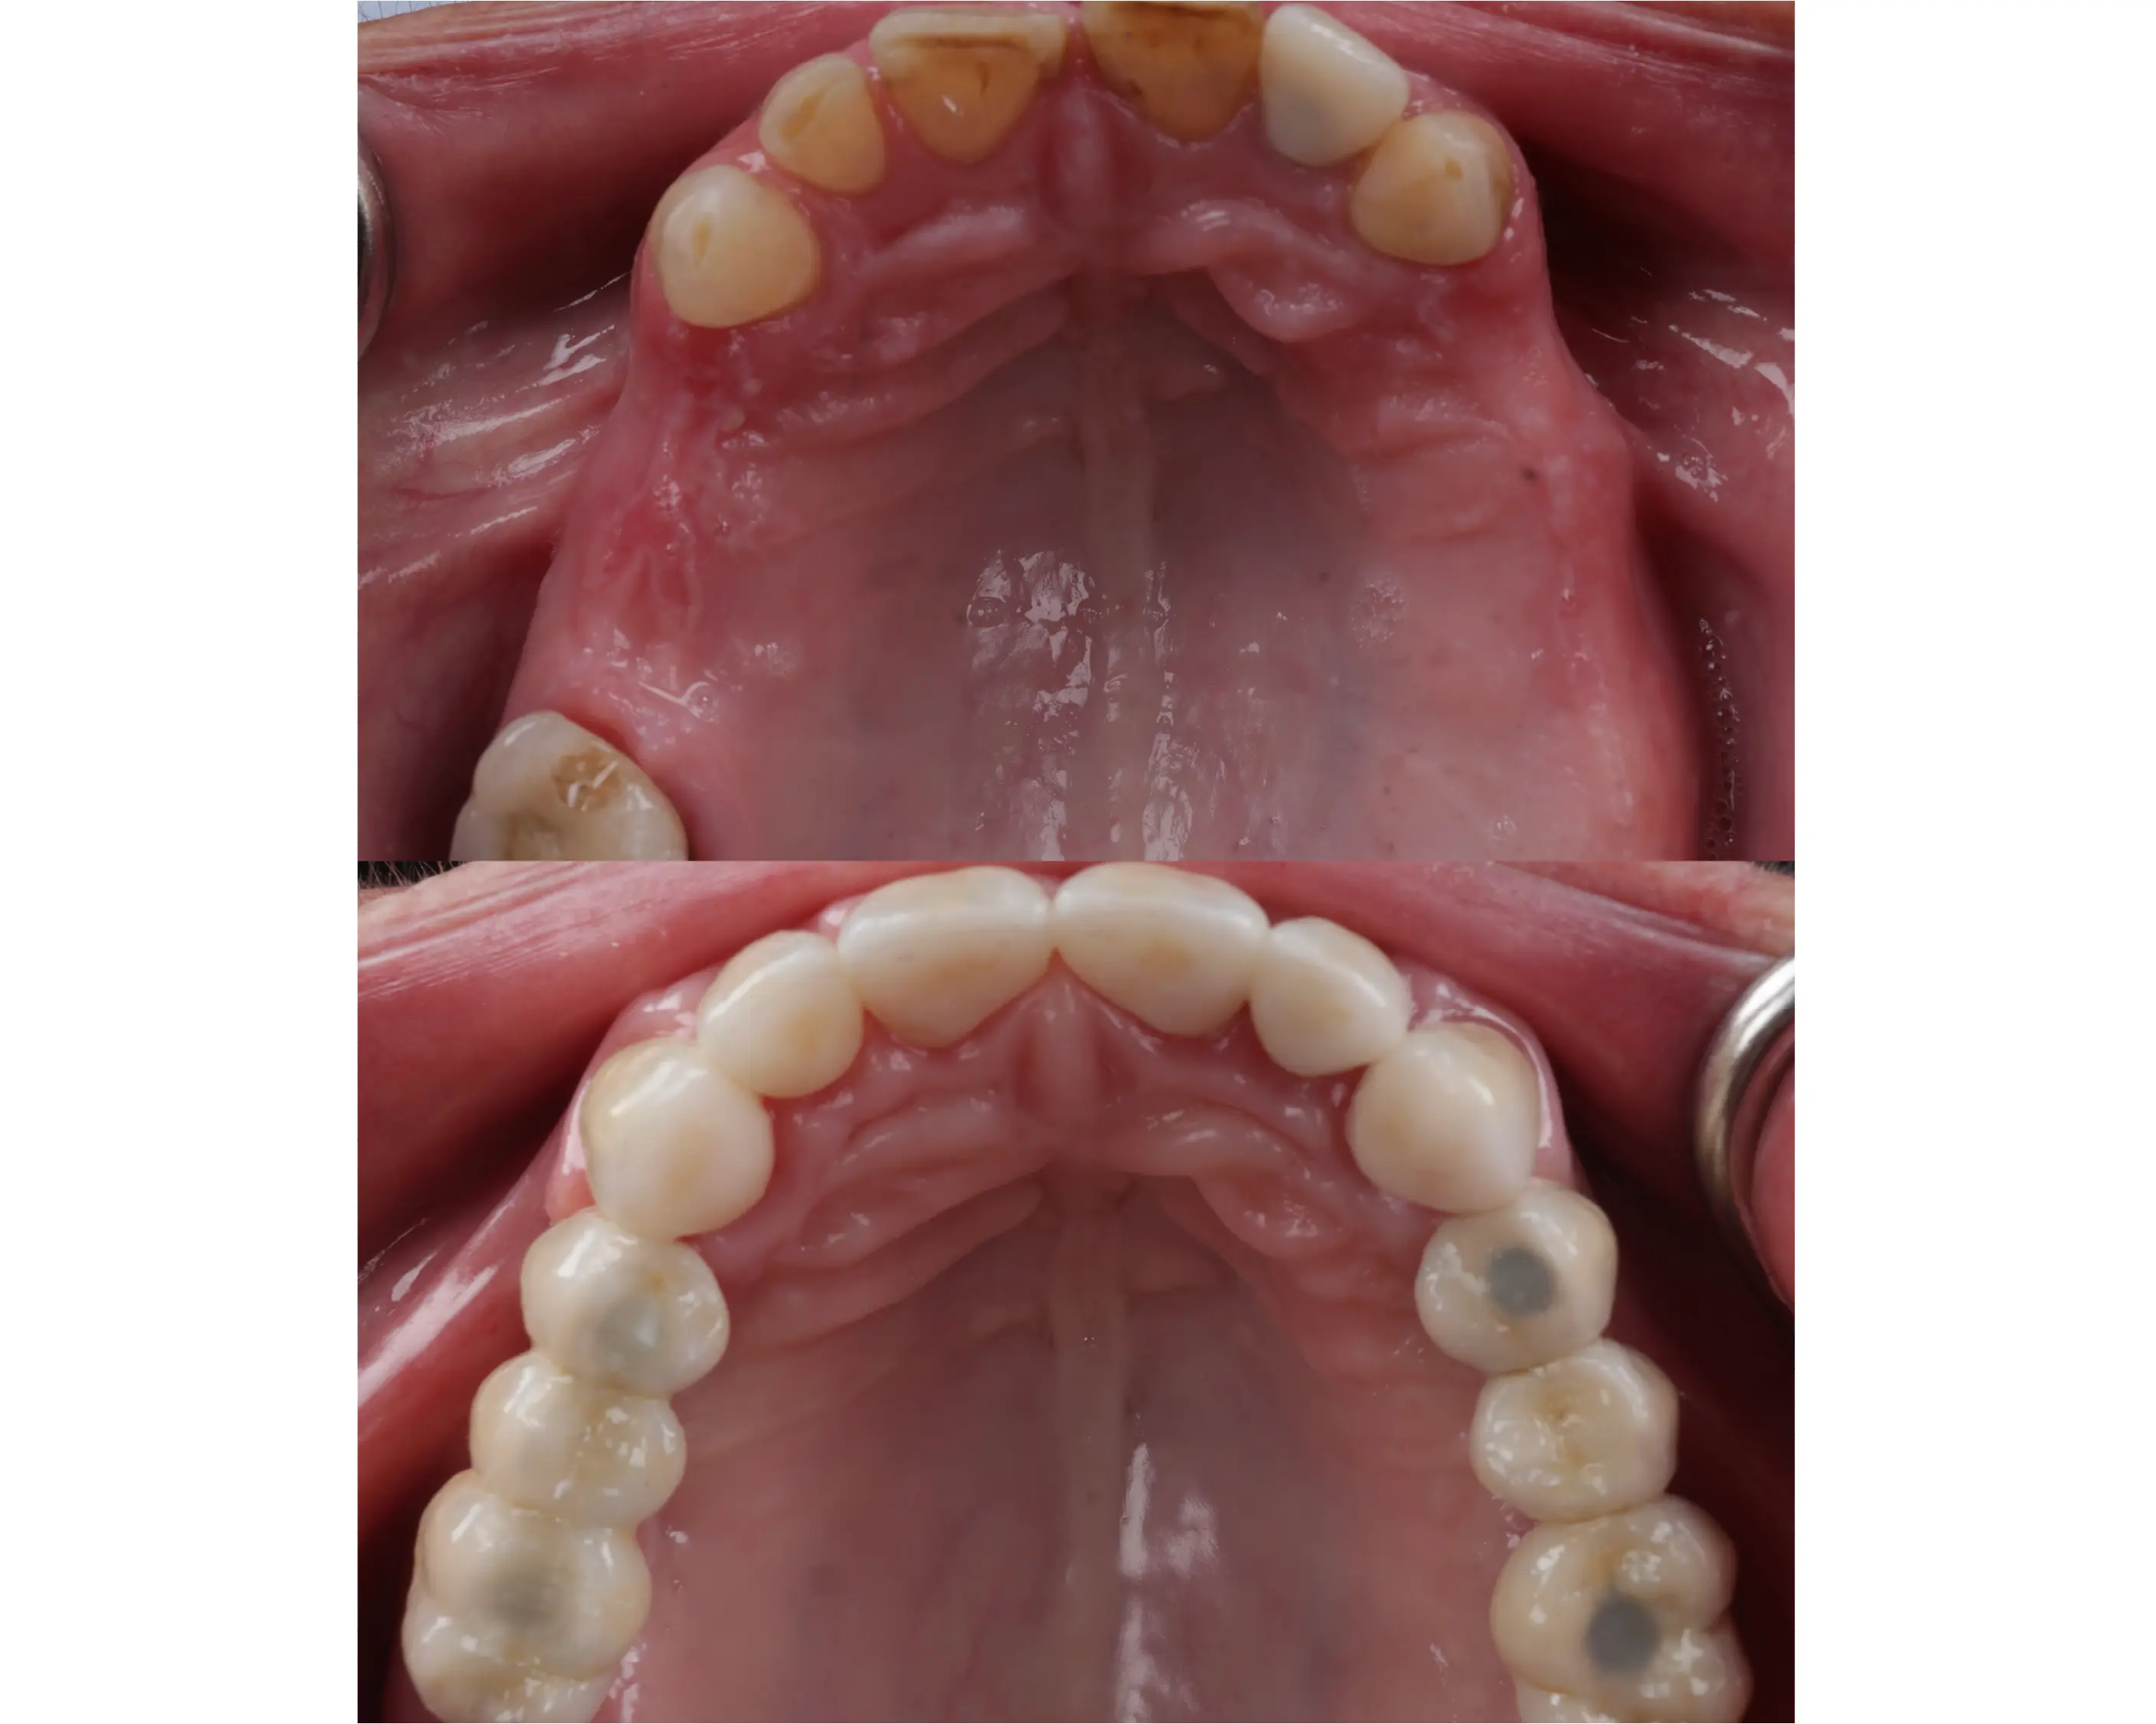

Denne 57-årige kvinde kom til os med et ønske om et smukkere smil og en mere velfungerende tyggeevne, da hun manglede flere tænder i overkæben. For at skabe balance og funktion blev biddet hævet med en kombination af plast og porcelæn. Derudover har vi lavet broer på implantater i begge sider af overkæben samt tre nye kroner i underkæben. Resultatet er et naturligt og harmonisk smil – og en markant forbedret tyggefunktion, der gør hverdagen lettere og mere behagelig.